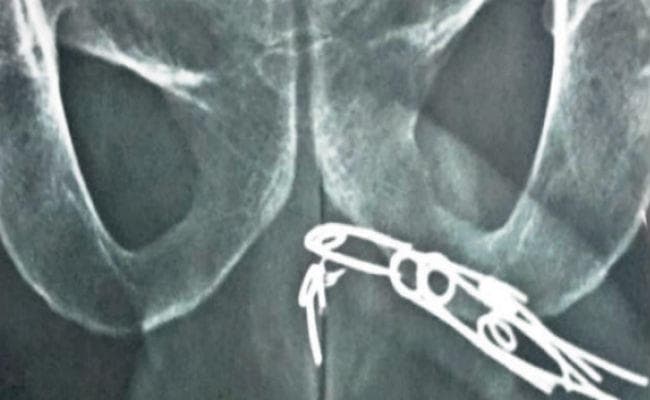

एक्स-रे रिपोर्ट से साफ हो गया है कि मरीज के गुप्तांग में पांच सेफ्टी पिन घुसी हुई है, जो मूत्रनली में जाकर फंस गयी हैं. मरीज का इलाज कर रहे डॉ सेन के सहयोगी चिकित्सक ने बताया कि आलपीन मूत्रनली में फंसी हुई है. इसे खींचकर बाहर निकालना असंभव है. इसलिए पहले माइक्रो सर्जरी कर आलपीन को बाहर निकालने की कोशिश की जायेगी. इस सर्जरी के सफल नहीं होने पर लिंग को चीरना पड़ेगा, क्योंकि आलपिन को खिंचकर बाहर नहीं निकाल सकतें.

एक्स-रे में हुआ खुलासा

इसके बाद घरवाले उसे नजदीकी डॉक्टर के पास ले गये. वहां एक्स-रे रिपोर्ट में इस बात का खुलासा हुआ कि युवक ने अपने गुप्तांग में पांच आलपीन घुसायी है. गांव में इसका इलाज संभव नहीं होने के कारण डॉक्टर ने मरीज को कोलकाता ले जाने की सलाह दी. इसके बाद घरवाले मरीज को लेकर यहां आये और रामकृष्ण मिशन सेवा प्रतिष्ठान में डॉक्टरों को दिखाया. चिकित्सकों ने बताया कि इसका एकमात्र उपाय सर्जरी ही है.